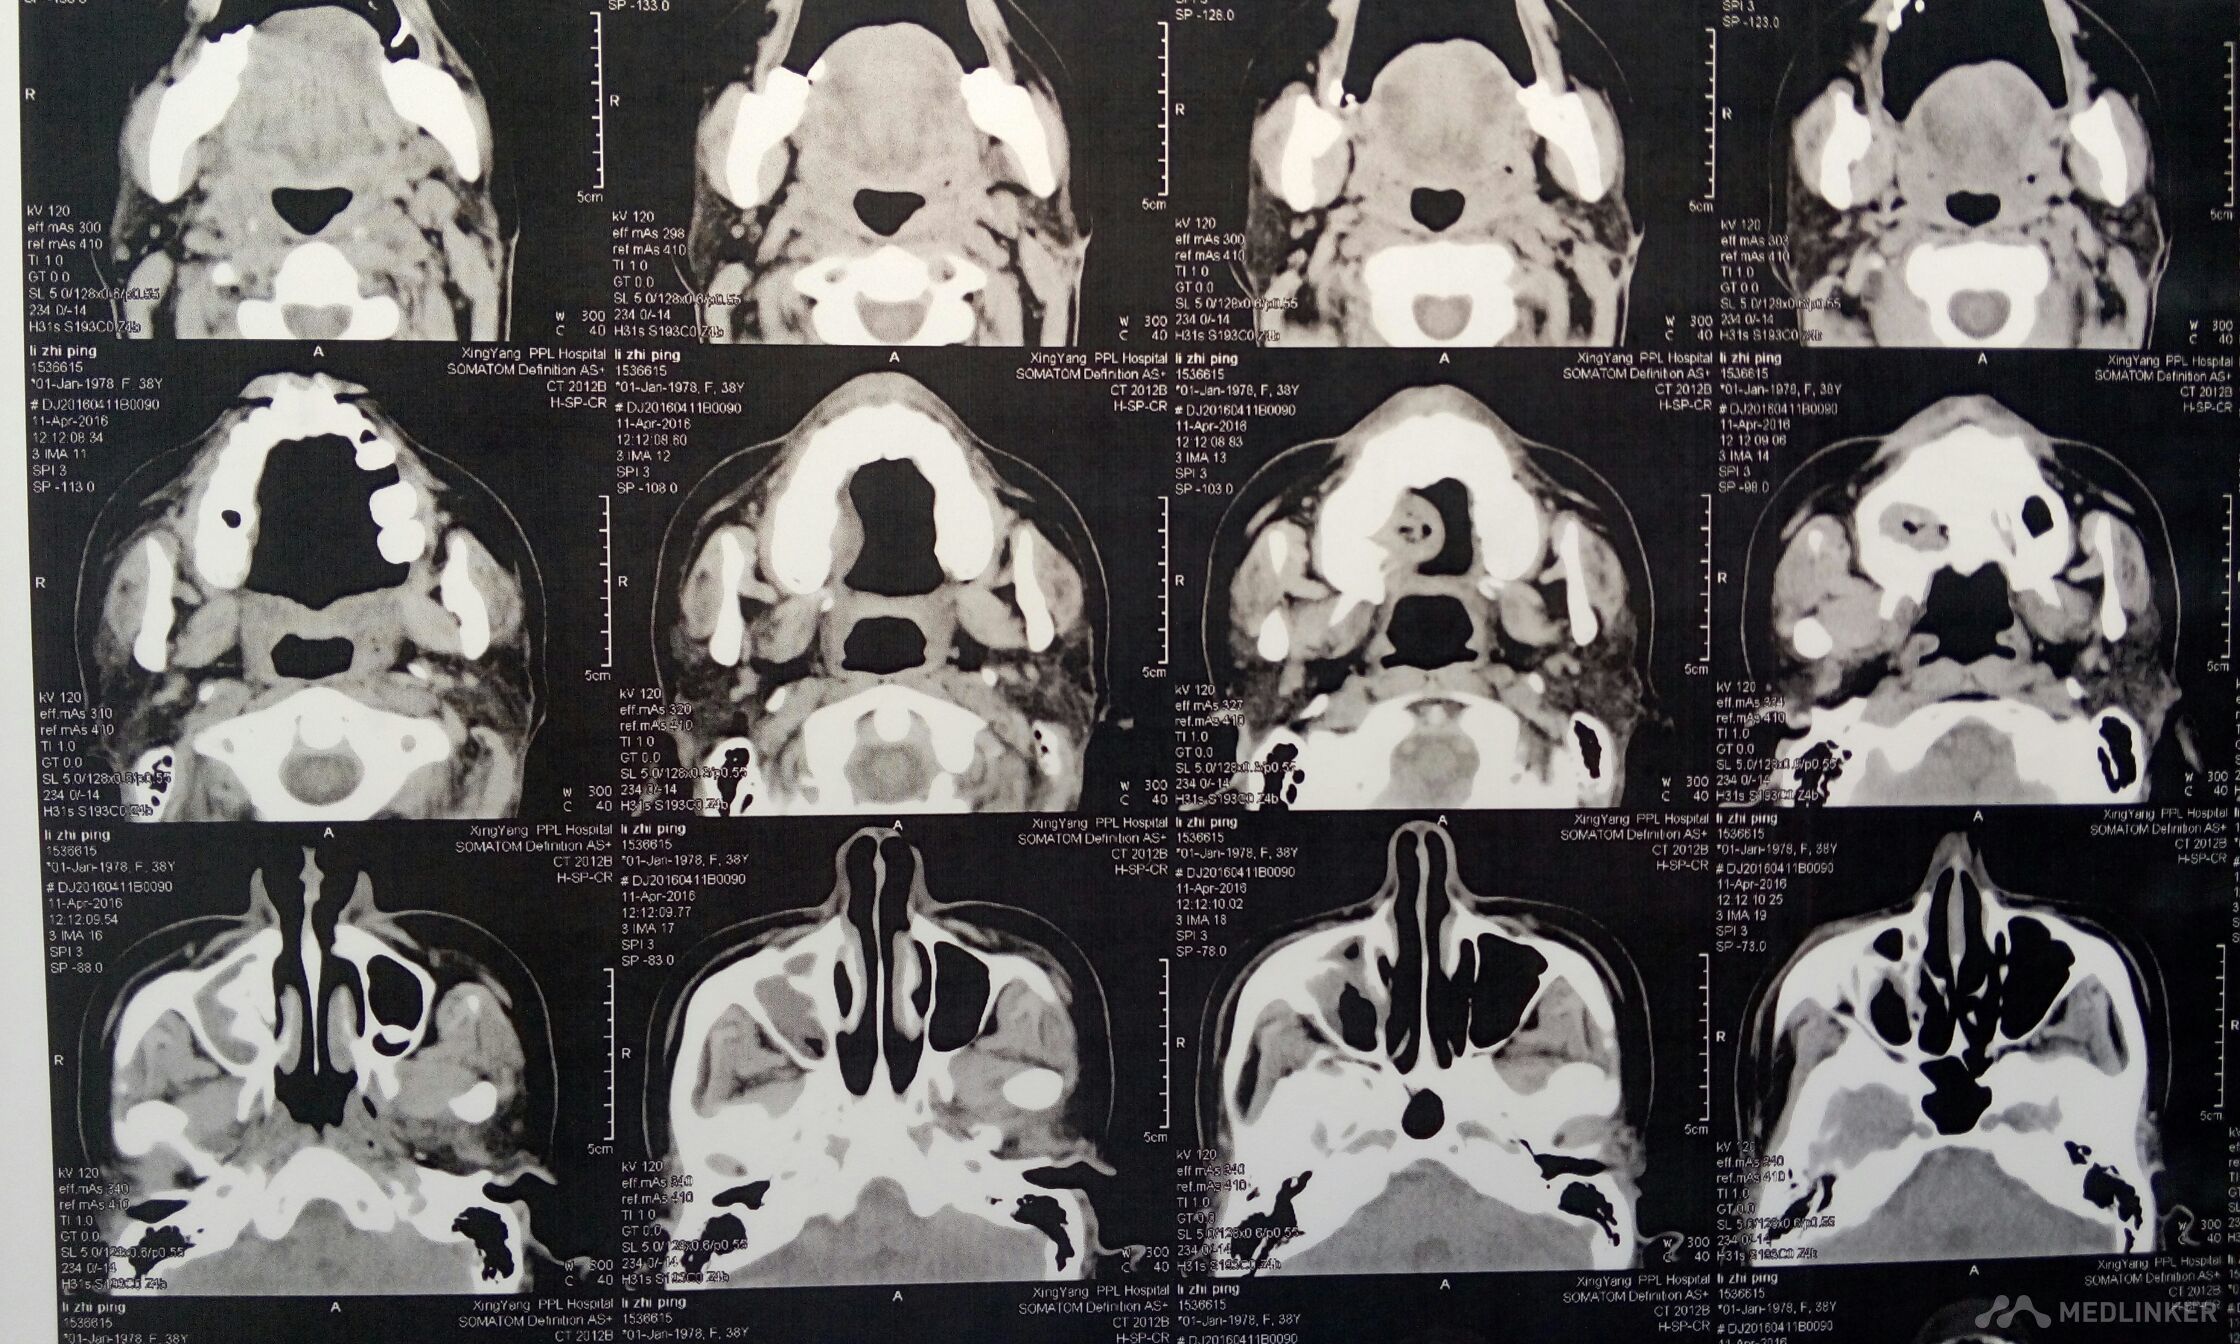

右侧上颌骨肿物,波及上颌窦,鼻腔。手术方案??

患者,女,38岁。因“发现右侧腭部肿痛一周”,来诊。查体:颌面部对称,张口度好。腭部右侧可见粘膜凸起肿物,约2*3cm,近中线处溃烂,有溢脓。CT检查可见肿物突入上颌窦及鼻腔,骨质破坏。现应用抗菌素治疗。拟行病理活检。请同仁看看手术方案?患者年轻,一侧上颌骨去除,假体如何修复?可否请鼻科联合手术,保留颌骨?